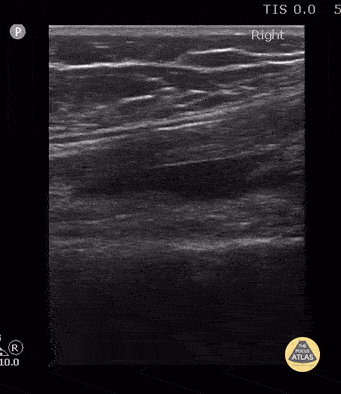

10 year old with moderate size knee effusion in the suprapatellar bursa (seen deep to the quadriceps tendon). Etiology due to lyme arthritis. Contributor: Antonio Riera, MD Yale University School of Medicine